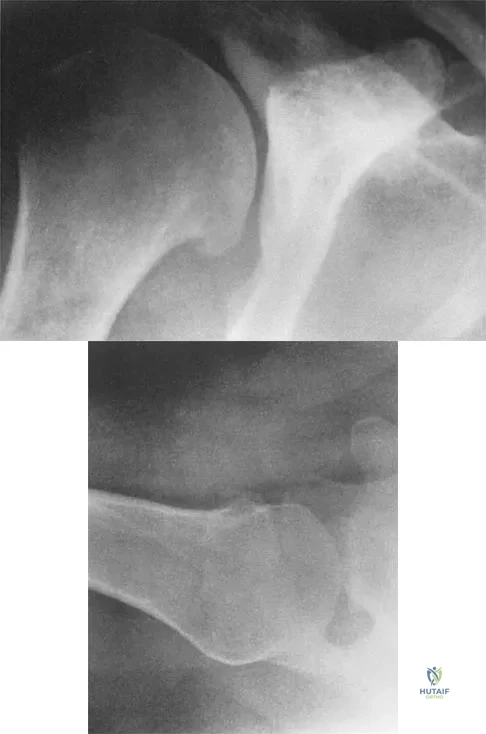

Figures 5a and 5b show the radiographs of a 45-year-old patient. What is the most likely diagnosis?

Explanation

Question 83

A 35-year-old man who is an avid weight lifter competing in local tournaments reports new onset pain and loss of motion in his dominant right shoulder. Examination reveals joint line tenderness, active elevation to 100 degrees, and external rotation to 10 degrees. His contralateral shoulder reveals 170 degrees forward elevation and 50 degrees external rotation. Radiographs are shown in Figures 46a and 46b. What is the next most appropriate step in management?